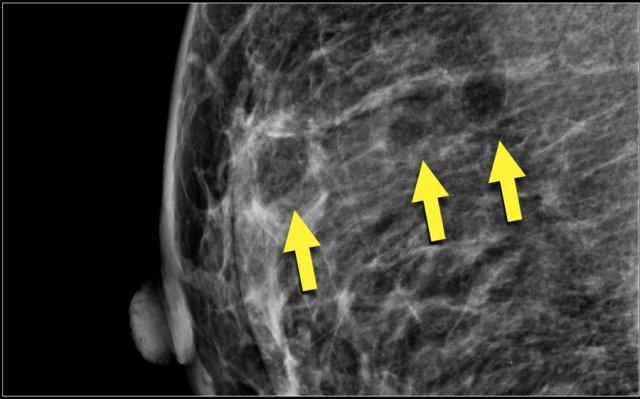

Lưu ý ở ví dụ bên trái, thành phần tuyến vú được phân loại là c – mật độ không đồng nhất, mặc dù thể tích mô tuyến xơ chiếm dưới 50%.

Mô tuyến xơ ở phần trên có mật độ đủ cao để che khuất các khối nhỏ.

Do đó được phân loại là c, vì các khối nhỏ có thể bị che khuất.

Theo phân loại cũ, trường hợp này sẽ được gọi là ACR 2: mật độ 25-50%.

Ví dụ bên phải có hơn 50% mô tuyến và cũng được phân loại là thành phần c.